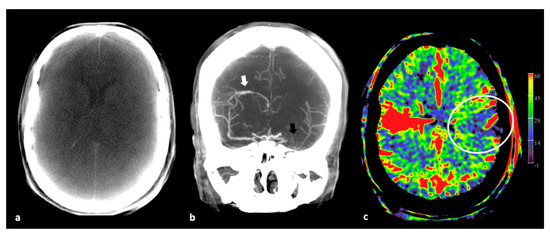

- Ava, L.; Berkefeld, J.; Lauer, A.; Seiler, A.; Pfeilschifter, W.; Müller-Eschner, M.; You, S.-J.; Weidauer, S.; Pilatus, U.; Wagner, M. Predictive Value of Pooled Cerebral Blood Volume Mapping for Final Infarct Volume in Patients with Major Artery Occlusions. A Retrospective Analysis. Clin. Neuroradiol. 2017, 27, 435–442. [Google Scholar] [CrossRef]

- Mueller, A.; Wagner, M.; Hattingen, E.; Seiler, A.; You, S.-J.; Samp, P.; Singer, O.C. Flat Panel Computed Tomography Pooled Blood Volume and Infarct Prediction in Endovascular Stroke Treatment. Stroke 2019, 50, 3274–3276. [Google Scholar] [CrossRef] [PubMed]